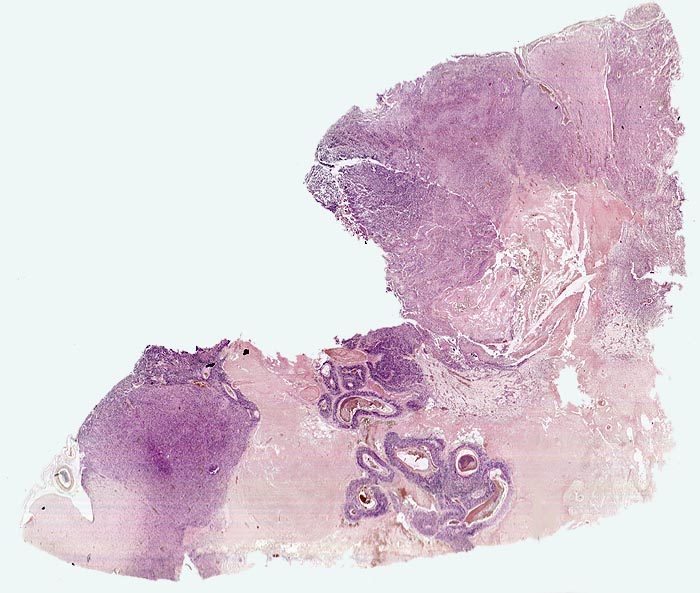

PathoPic – image database / PathoPic ID 5197 - Glioblastoma multiforme (WHO IV)

Glioblastoma multiforme (WHO IV)

Das Tumorgewebe erscheint aufgrund seiner Zelldichte blau. Die Grenze zum Hirnparenchym ist unscharf. In der Übersicht sind flächenhafte ischämische Tumornekrosen infolge einer ungenügenden Sauerstoffversorgung. Im Zentrum der Nekrose sind thrombosierte Gefässe umgeben von einem schmalen blauen Saum vitaler Tumorzellen erkennbar.